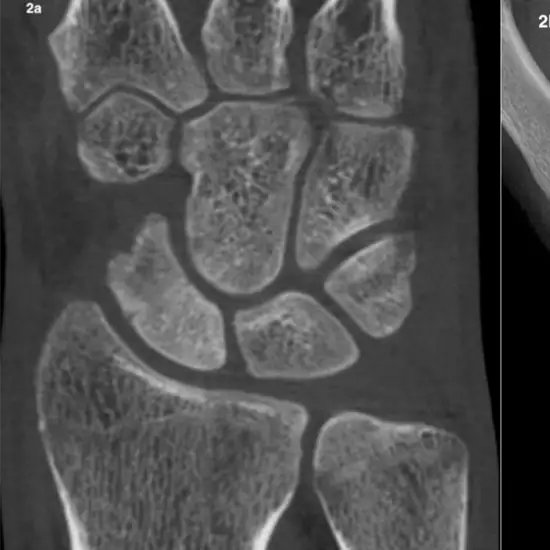

CT CT 3D Left Scaphoid (3-dimensional Computed Dimension of Left Scaphoid) is an imaging scan used to obtain 3-D images of the left scaphoid. The left scaphoid is one of the thumb-side small carpal bones of the left wrist that is important for the motion and stability of the wrist. This scan helps detect the location of the scaphoid in the left wrist and scaphoid fracture.

CT 3D left scaphoid is prescribed by the doctors to get a clearer picture of the scaphoid to diagnose a scaphoid fracture, and the location of the scaphoid bone to confirm if it's displaced or not. It is also used when a patient experiences the symptoms such as pain and swelling in the anatomic snuffbox and on the thumb side of the left wrist.